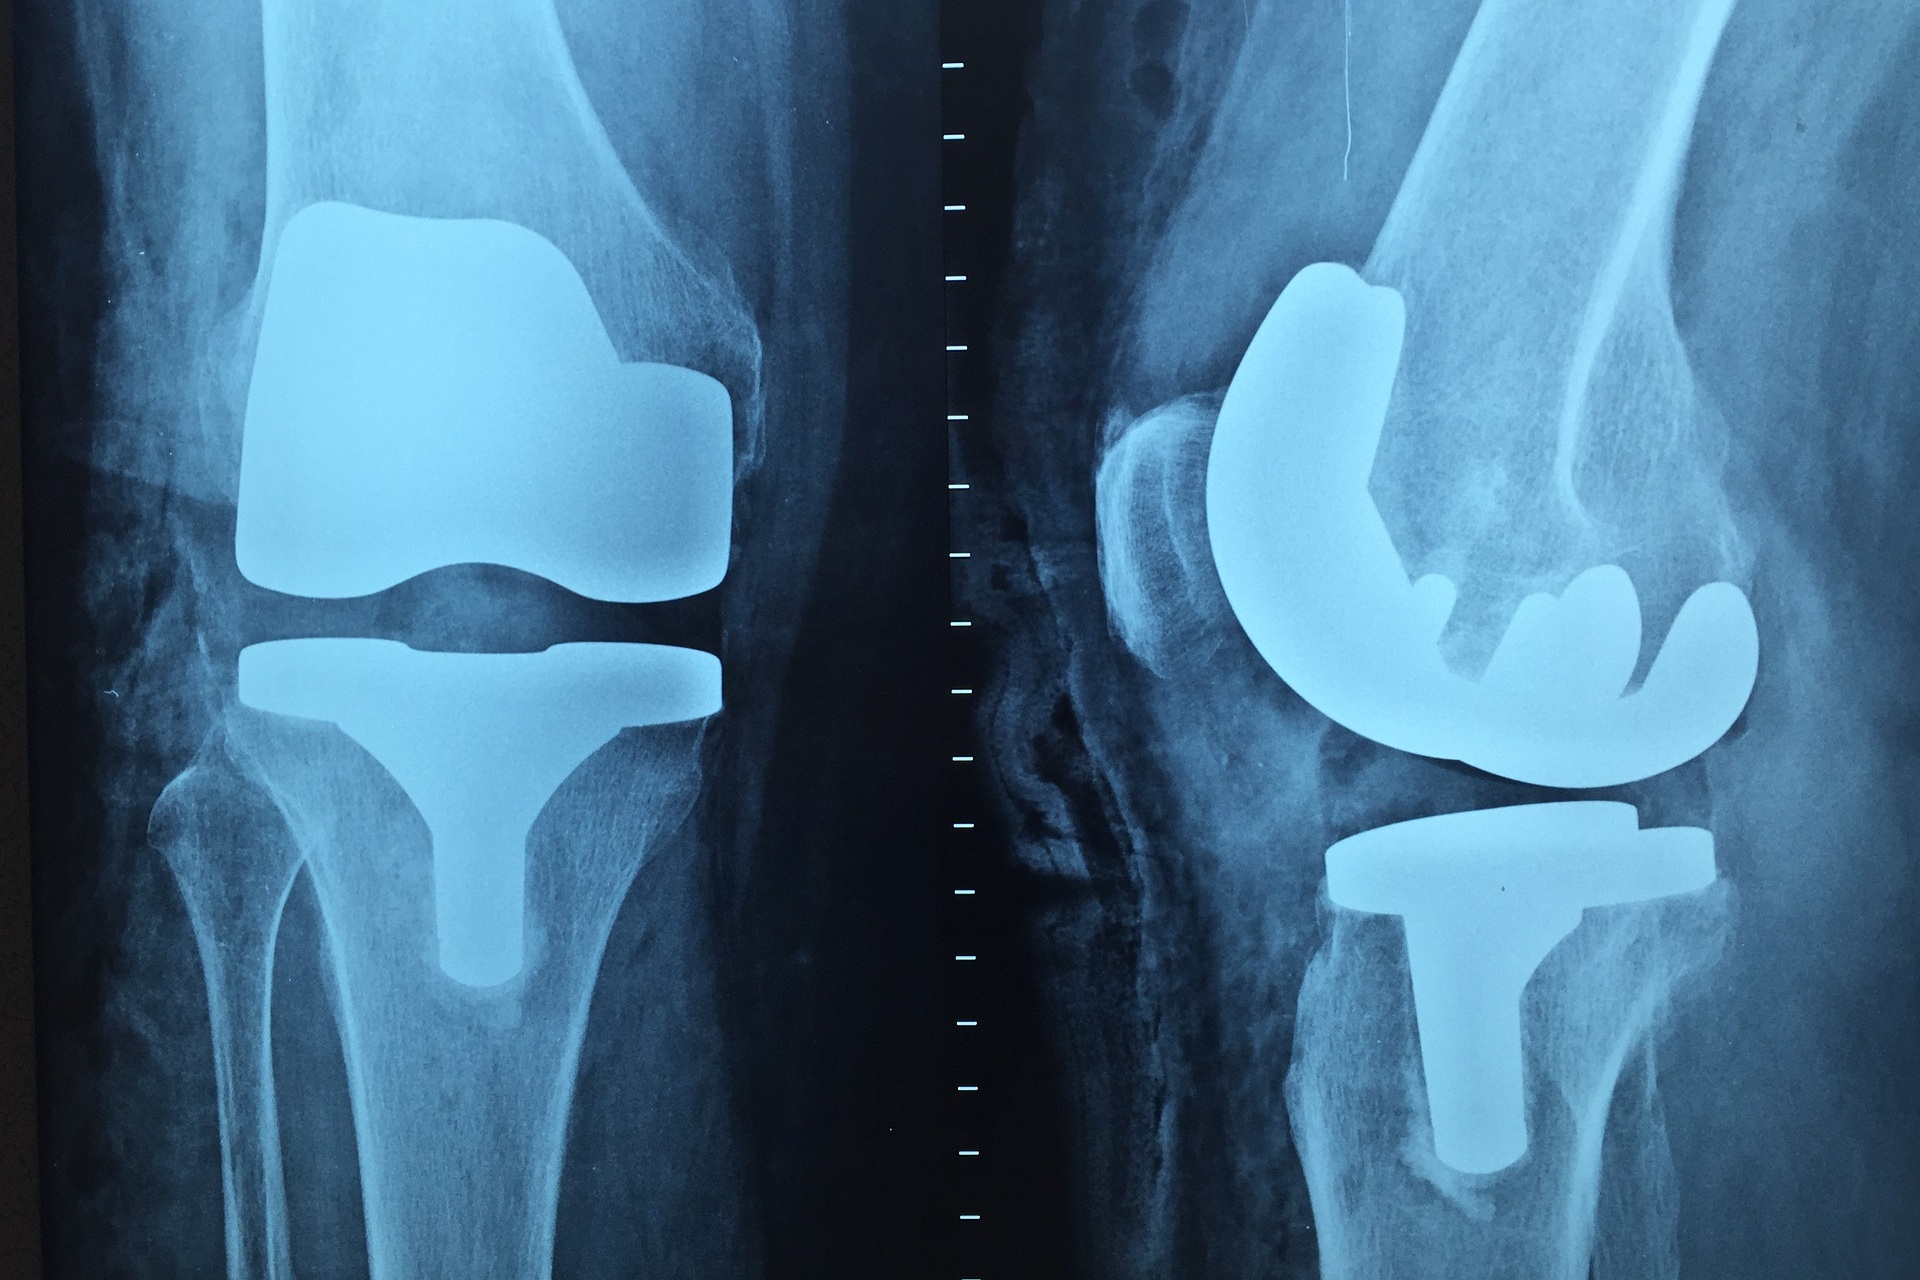

Rehabilitace je nejčastěji nutná po ortopedických operacích, ale také například po amputacích a samozřejmě po úrazech. „Rehabilitace v podstatě začíná už první pooperační den,“ říká host. Nejčastěji spočívá ve cvičení s fyzioterapeutem.